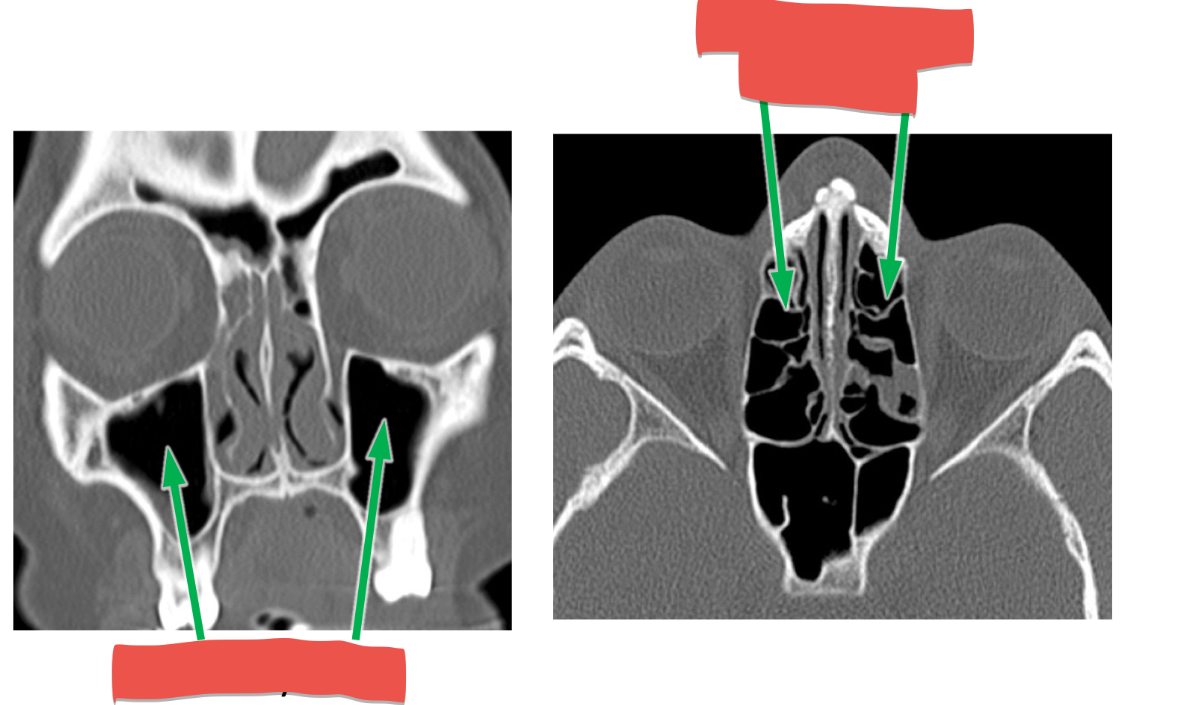

CN I: Olfactory Nerve function and exit:

smell and cribriform plate

CN V2 Maxillary Division function and exit:

GENERAL SENSORY: Nasal mucosa, palate, nasopharynx, maxillary sinus, maxillary gums & teeth, cheeks, lower eyelid, upper lip

Foramen rotundum